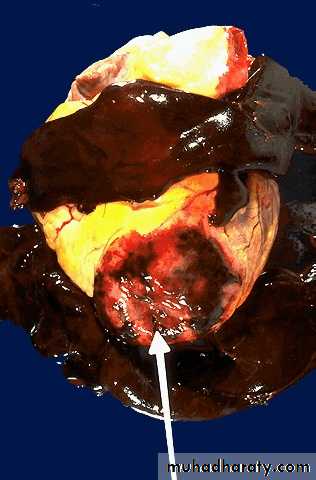

collagenization following healing of a subendocardial myocardial infarction (remote}.• One complication of a transmural myocardial infarction is rupture of the myocardium. This is most likely to occur in the first week between 3 to 5 days following the initial event, when the myocardium is the softest. The white arrow marks the point of rupture in this anterior-inferior myocardial infarction of the left ventricular free wall and septum. Note the dark red blood clot forming the hemopericardium. The hemopericardium can lead to tamponade.

In cross section, the point of rupture of the myocardium is shown with the arrow. In this case, there was a previous myocardial infarction 3 weeks before, and another myocardial infarction occurred, rupturing through the already thin ventricular wall 3 days later.